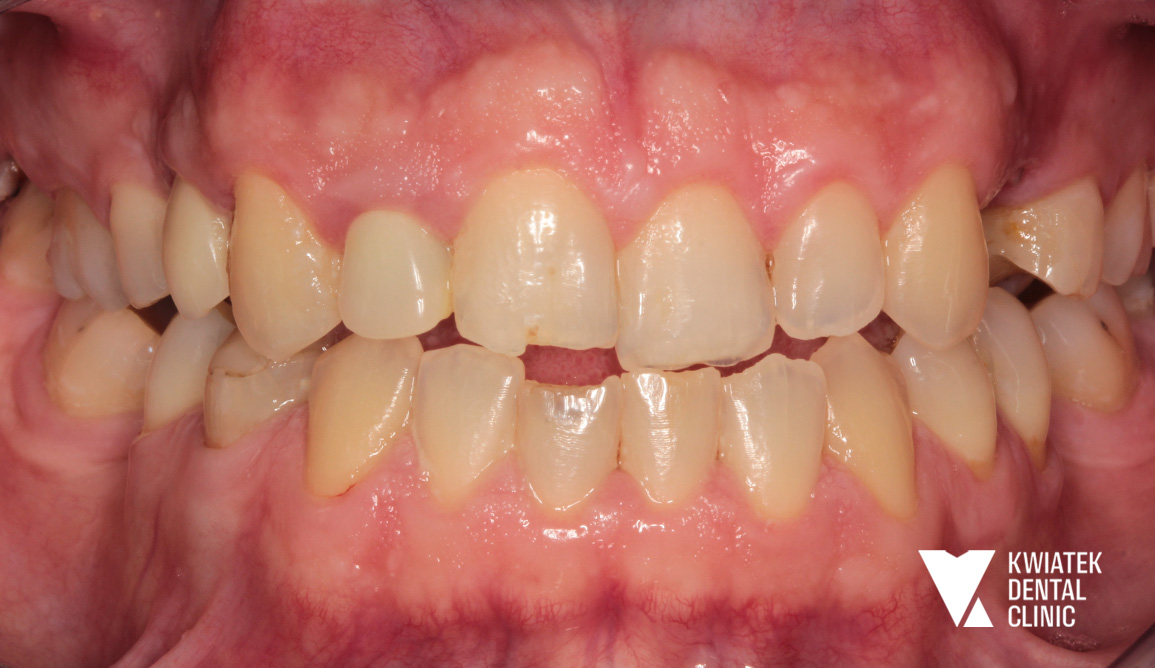

Pierwsze etapy leczenia ujawniły złożony obraz kliniczny:

Równolegle prowadzono leczenie zachowawcze oraz endodontyczne, eliminując ogniska próchnicy i odbudowując zęby. Istotnym elementem była również poprawa higieny jamy ustnej, wsparta profesjonalnymi zabiegami i edukacją.

Po odbudowie fundamentów rozpoczęto leczenie ortodontyczne, którego celem była korekta ustawienia zębów i przygotowanie optymalnych warunków dla finalnej estetyki.